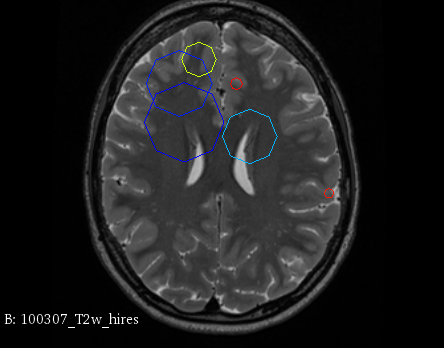

Figure 3 provides a scale-space visualization of feature matches for a single pair of MZ twins and NT siblings, where scale information is represented using the circle radius. Note that circles represent the intersection of 3D spheres with the visible slice and, thus, non-intersecting features are hidden in this 2D visualization.

It can be seen that different image modalities generally result in distinct, complementary feature correspondences throughout the brain, allowing a rich characterization of both anatomical and connectivity structure. In T1 and T2 images, features are mainly located in the frontal lobe, corpus callosum and brain stem. Smaller-scale features are also visible along various cortical regions, as well as in sub-cortical structures near the basal ganglia. Although highly correlated, T1 images show significantly more feature matches than T2 images. Moreover, images based on diffusion measures have less matches than in structural modalities. These matches are located mostly inside or near to white matter: larger-scale features in the corpus-callosum, and smaller-scale ones in the brain stem and along white matter bundles. While not shown in the figure, the set of matches found by combining two modalities (e.g., T1 + T2) generally corresponds to the union of those obtained with these individual modalities.

Comparing different sibling types, we observe a greater number of matches between MZ twins than NT siblings. This observation, which is easier to visualize in T2 and GFA images, is consistent with other analyses on twin datasets. In terms of feature location and scale, no obvious pattern can be seen when comparing these two sibling types. However, a more detailed analysis would be required to validate this assertion.